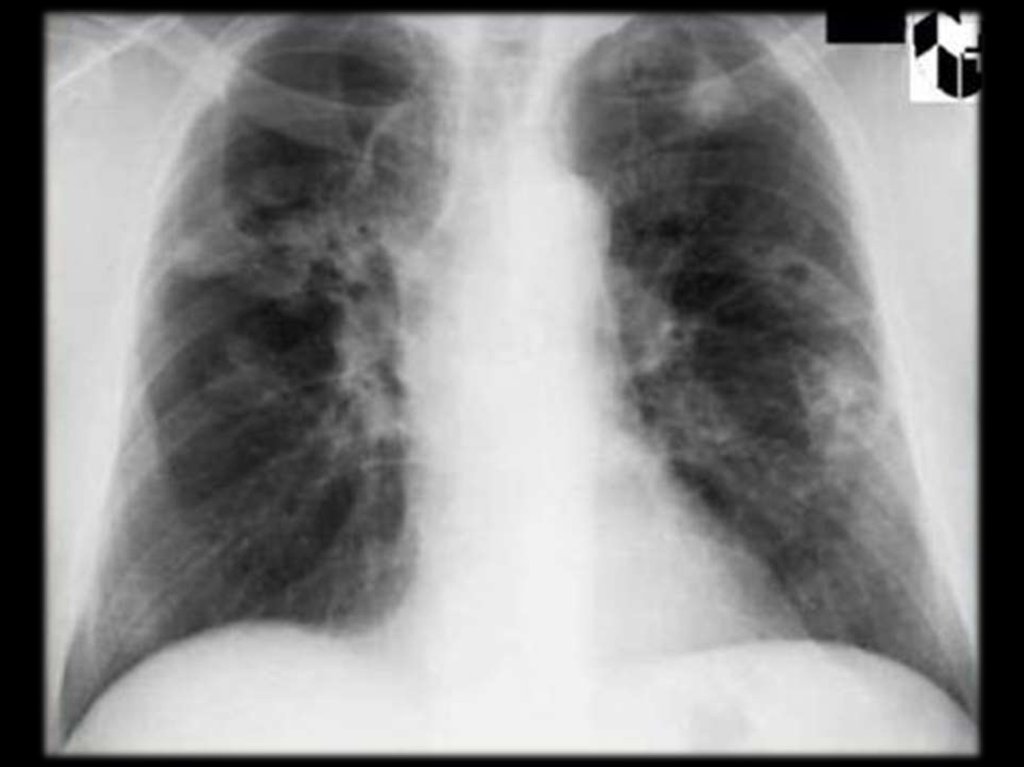

6.

Поражение

лёгких

встречается

практически у всех больных: кашель,

иногда

надсадный,

боль

в

груди,

одышка, кровохарканье.

Аускультативная картина весьма скудная.

R-признаки

лёгочной

патологии

разнообразны:

узлы,

инфильтраты,

образование

полостей,

очаговые

ателектазы, экссудативный плеврит.

2. изменения в лёгких при R-исследовании:

узелки, инфильтраты или полости в лёгких;